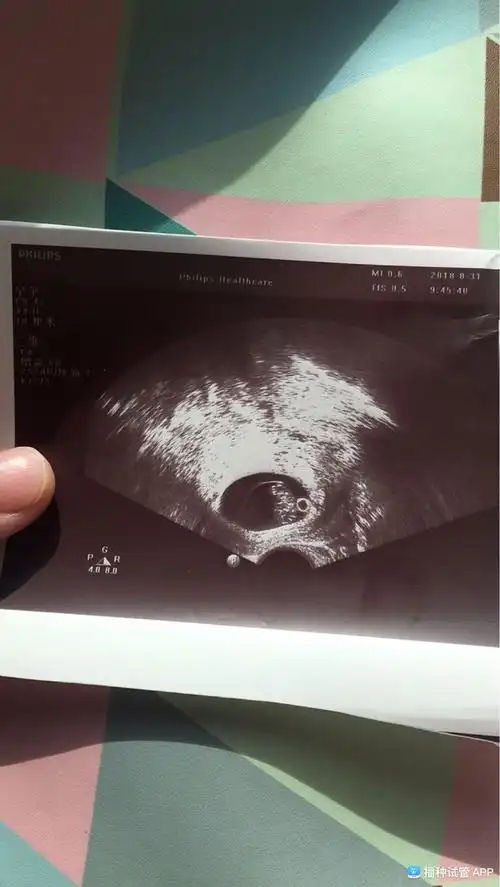

亲们谁会看b超单,8周的b超,孕囊里那个白色小圈圈是啥

早孕期(12周之前) 怀孕后的您,多数会在妊娠6-8周做第一次b超检查

怀孕8周,孕囊直径多大?孕8周的注意事项,孕妈不妨看看